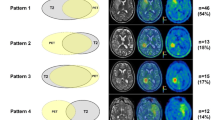

We compared three different volumetric tools using calibrated phantoms and serial MRIs of patients with neurofibromatosis 2 and VS. We expected very accurate volume estimates for all of the phantoms because of their bright contrast and smooth, flat edges. However, none of the three software tools tested was able to calculate an accurate volume for the phantoms. In fact, OsiriX and BrainLab underestimated the actual size of the phantoms while ITK-Snap calculated volumes significantly above the real volume. The demarcation of the boundary is essential for calculating reliable volumes; this may be impeded in very small or insufficiently confined objects (Fig. 4). Both OsiriX and BrainLab provided volume estimates that were close to the true volumes of the 2 ml, 3 ml, 5 ml and 8 ml phantoms, but the volume estimates obtained with ITK-Snap were significantly greater than the true volumes of all of these phantoms. However, BrainLab produced even more accurate results for smaller phantom sizes than for larger. This association is remarkable, because it contrasts to the intuitive assumption that the precision of smaller measurements would be worse than for larger measurements. The relative miscalculation of the 1 ml phantom could be due to a blurrier border of the sharp edges (Figs. 1 and 4). Another factor might be the number of slices that cover one object. For flat objects the inter-slice volume-loss might be relatively bigger than for compact or spherical objects.